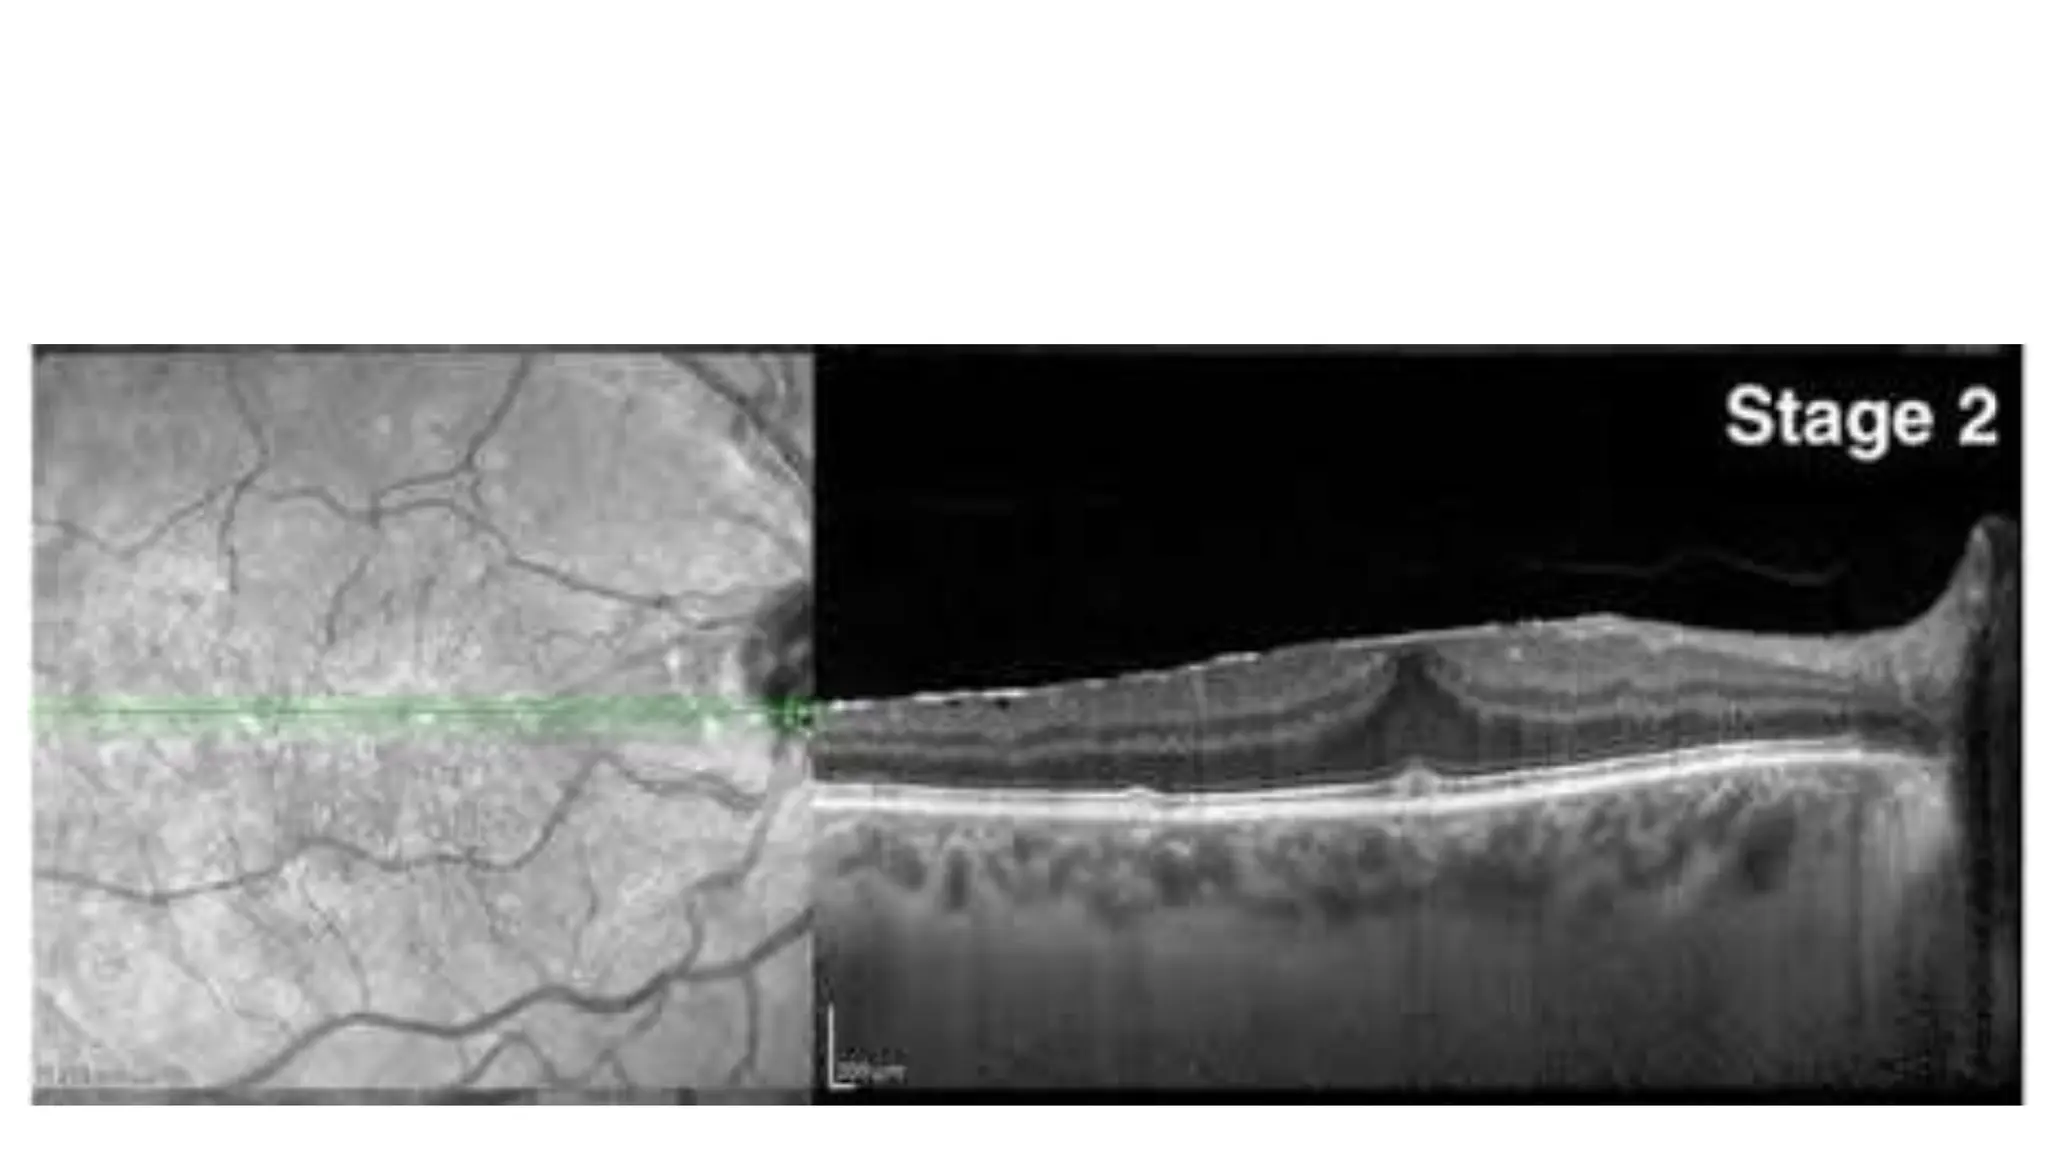

The document discusses various stages of posterior vitreous detachment (PVD) and associated ophthalmological conditions. It highlights the classification of PVD stages, including no PVD, paramacular PVD, and complete PVD, alongside related factors like traction and retinal issues. Key acronyms and terms relevant to diabetic retinopathy and retinal morphology are also mentioned.